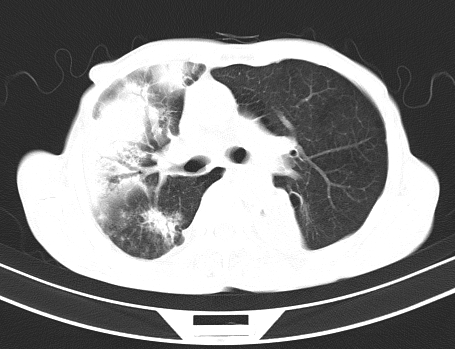

以下是引用gaoshengjiang在2008-5-30 19:53:00的发言:[br]右上叶可见大片实变影,其内可见充气支气管影及囊状影,右上叶尖端支气管走形区可见结节样影,左侧胸腔内可见胸腔胃影。纵隔淋巴结肿大。[br]考虑:1.右上肺阻塞性肺炎伴肺脓肿形成。支持转移所致。[br] 2.左侧胸腔胃。